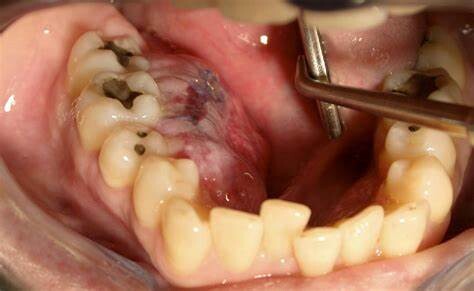

Individuals with osteosarcoma of the jaw most commonly complain of swelling (this is different than with long bone osteosarcoma, where the most common complaint is bone pain during activity). Other osteosarcoma of the jaw symptoms may include:

Ulcerations

The course of treatment recommended for osteosarcoma of the jaw will vary from one patient to another. With that being said, physicians often recommend surgically removing the cancer from the jawbone. Because the jawbone is considerably more delicate and complex than longer bones in the body, jaw osteosarcoma surgery can be particularly challenging. Treatment for osteosarcoma of the jaw may also involve chemotherapy and/or radiation therapy.